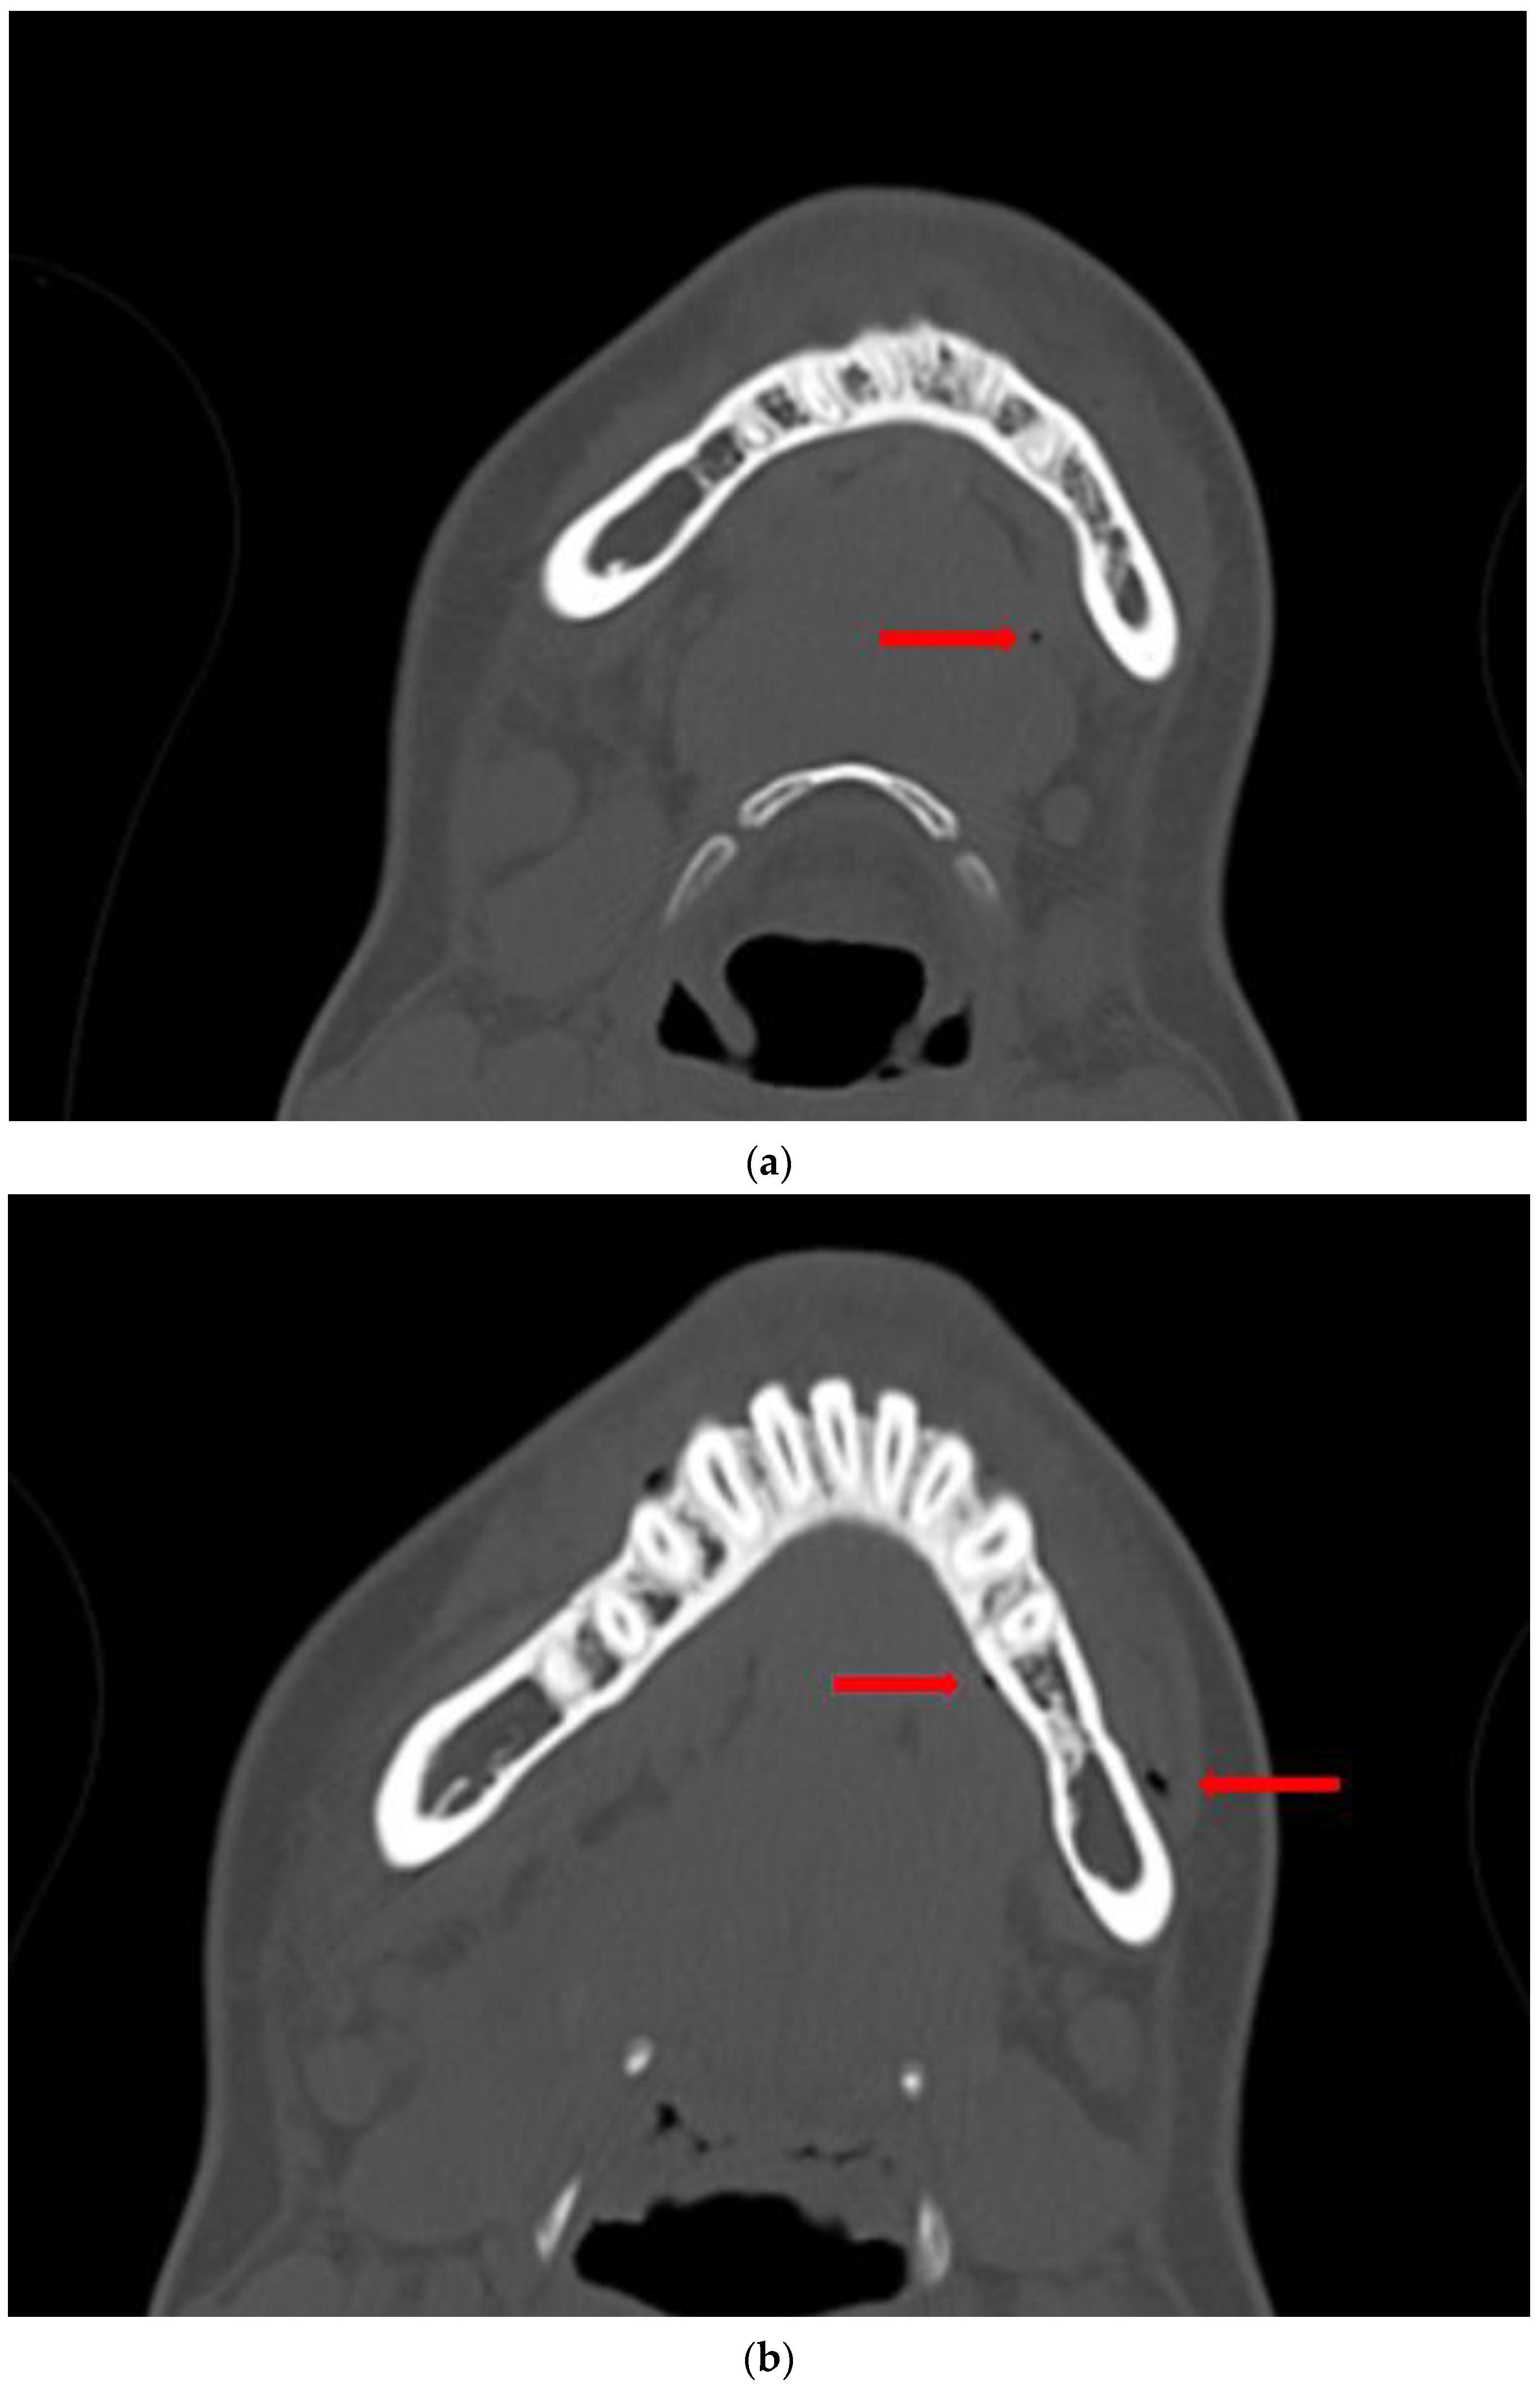

3.1. Case 1

3.2. Case 2